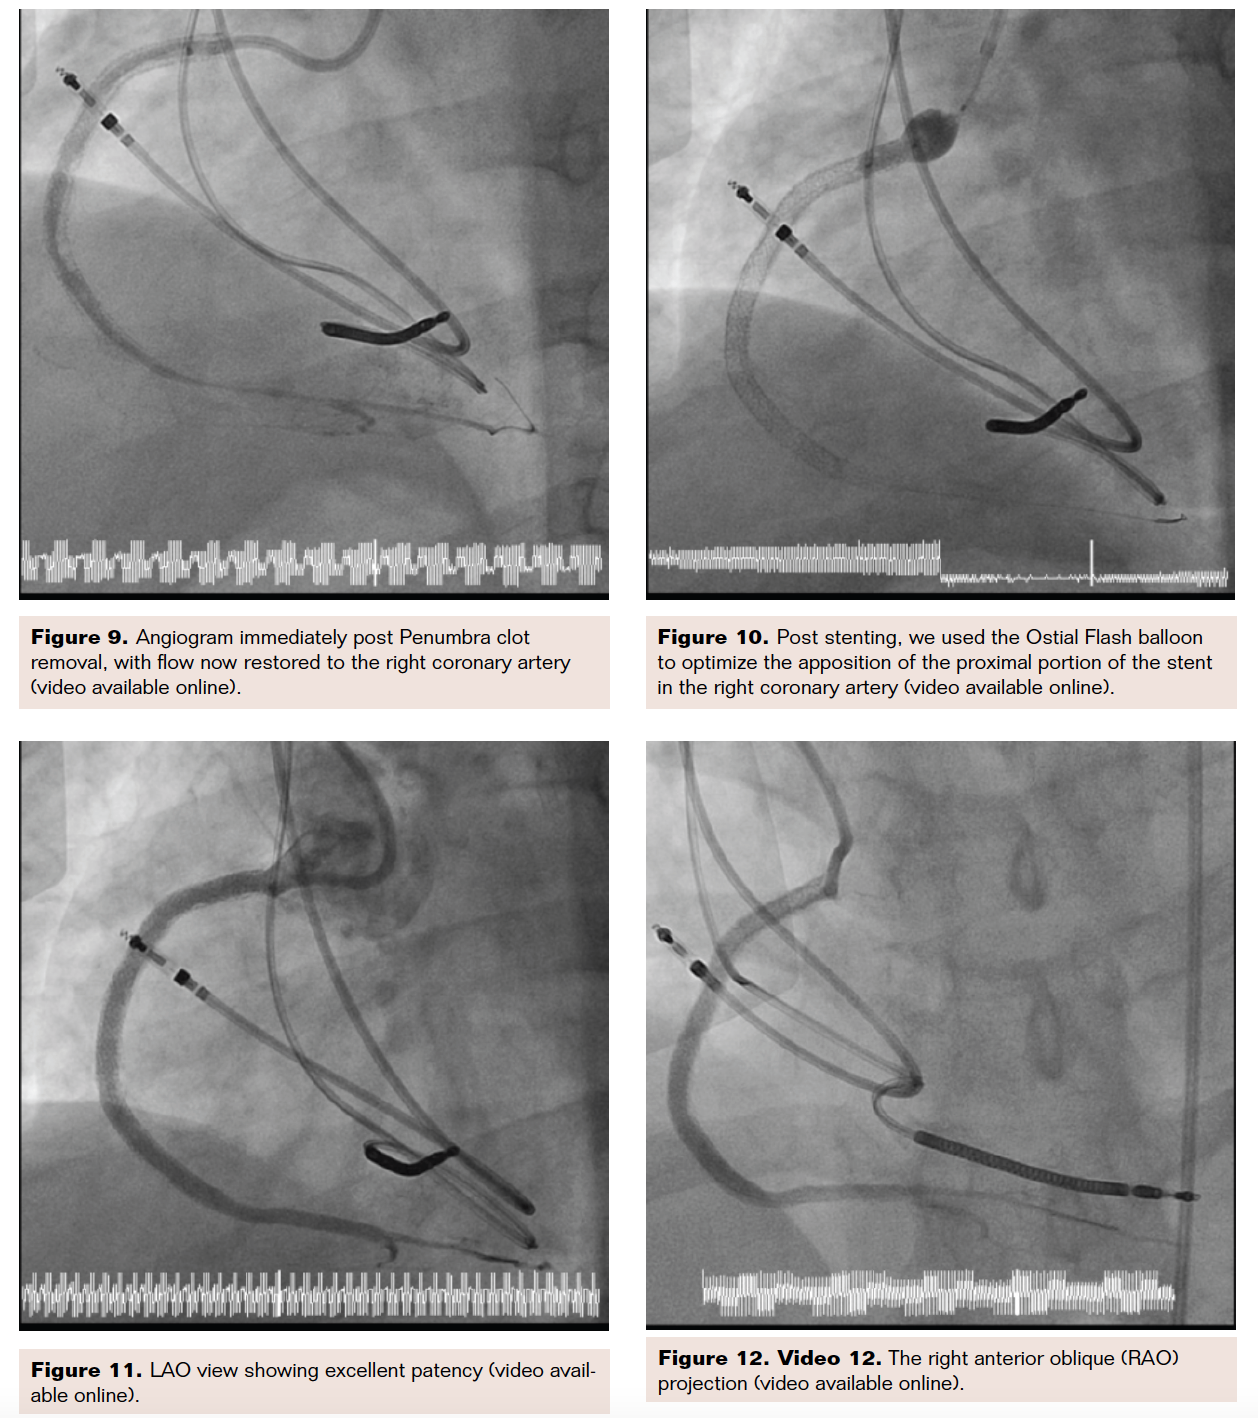

There was an excessive amount of plaque and thrombus in the vessel, so the McNamara catheter (Medtronic) was inserted and 4 mg of intra-arterial tissue plasminogen activator (tPA) was infused in the occluded vessel (Figures 6-8). After re-inserting the .014-inch wire, five slow passes were made with the Indigo CAT RX aspiration catheter in order to remove thrombus from the totally occluded vessel. Afterwards, an angiogram confirmed TIMI-3 flow with no more thrombus observed, but the vessel was diffusely diseased (Figure 9). We performed balloon angioplasty and subsequent stenting, placing a 2.75 × 38 mm Resolute Onyx drug-eluting stent (Medtronic) distally and two 4.5 × 38 mm drug-eluting stents proximally. At the origin of the vessel, a 5 × 20 mm drug-eluting stent was placed using an Ostial Flash balloon (Ostial Corporation) to optimize the origin of this stent (Figure 10). Following this final procedure, angiography demonstrated a widely patent RCA with TIMI-3 flow (Figures 11-12).